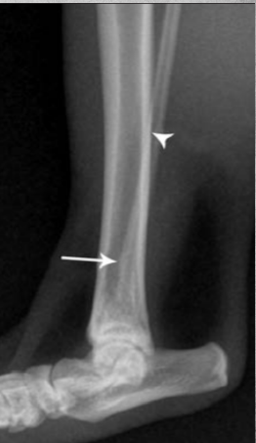

Describe Premature closure of growth plate.

e.g. distal ulna such as in image

results in growth discrepancy and may disrupt the function of the joint

What does this depict?

Premature closure of growth plate distal radius.